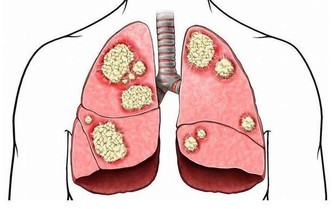

四、排除肺臟毒素檢查肺臟是否有毒的方法:1、皮膚呈銹色,晦暗中醫認為肺管理全身的皮膚,皮膚是否潤澤、白皙,都要依靠肺的功能良好。

當肺中毒素比較多時,毒素會隨著肺的作用沉積到皮膚上,使膚色看起來沒有光澤。

2、便秘中醫認為,肺臟和大腸是一套系統,當上面肺臟有毒素時,下面腸道內也會有不正常淤積,就出現了便秘。

3、多愁善感,容易悲傷毒素在肺,會干擾肺內的氣血運行,使得肺臟不能正常舒暢胸中的悶氣,被壓抑得多愁善感起來。